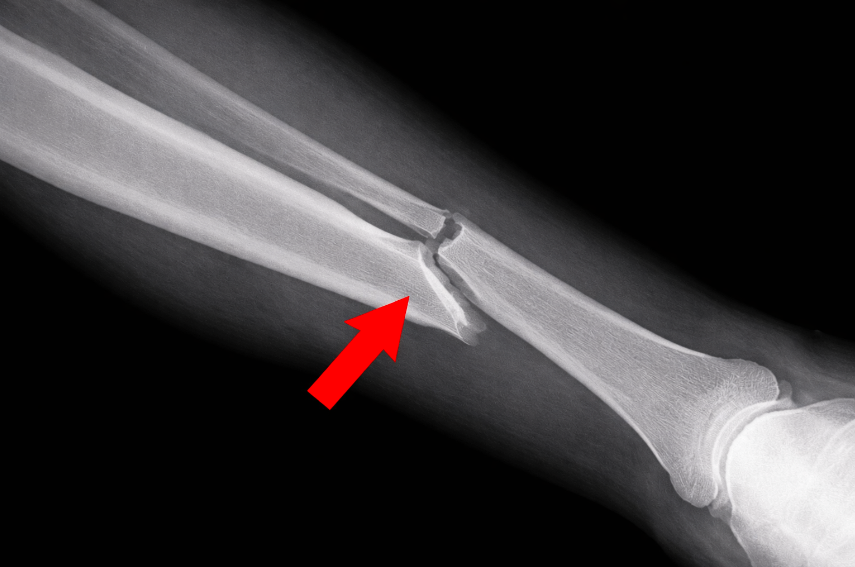

How is a Fibula Fracture Diagnosed?

Diagnosis involves clinical assessment and imaging. A healthcare professional may:

Request X-rays to confirm the fracture

Use CT scans or MRI if further detail is required

Accurate diagnosis is important, particularly where the ankle joint is involved.